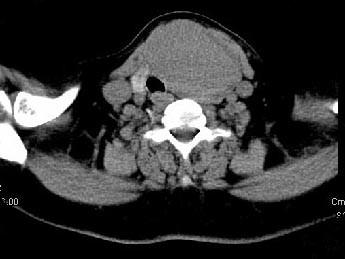

问题 女,56岁 ,发现颈部肿块一月余,CT如图所示,最可能诊断为 ( )

选项 A、甲状腺腺瘤 B、甲状腺脓肿 C、甲状腺乳头状癌 D、甲状腺原发淋巴瘤 E、甲状舌管囊肿

答案 A